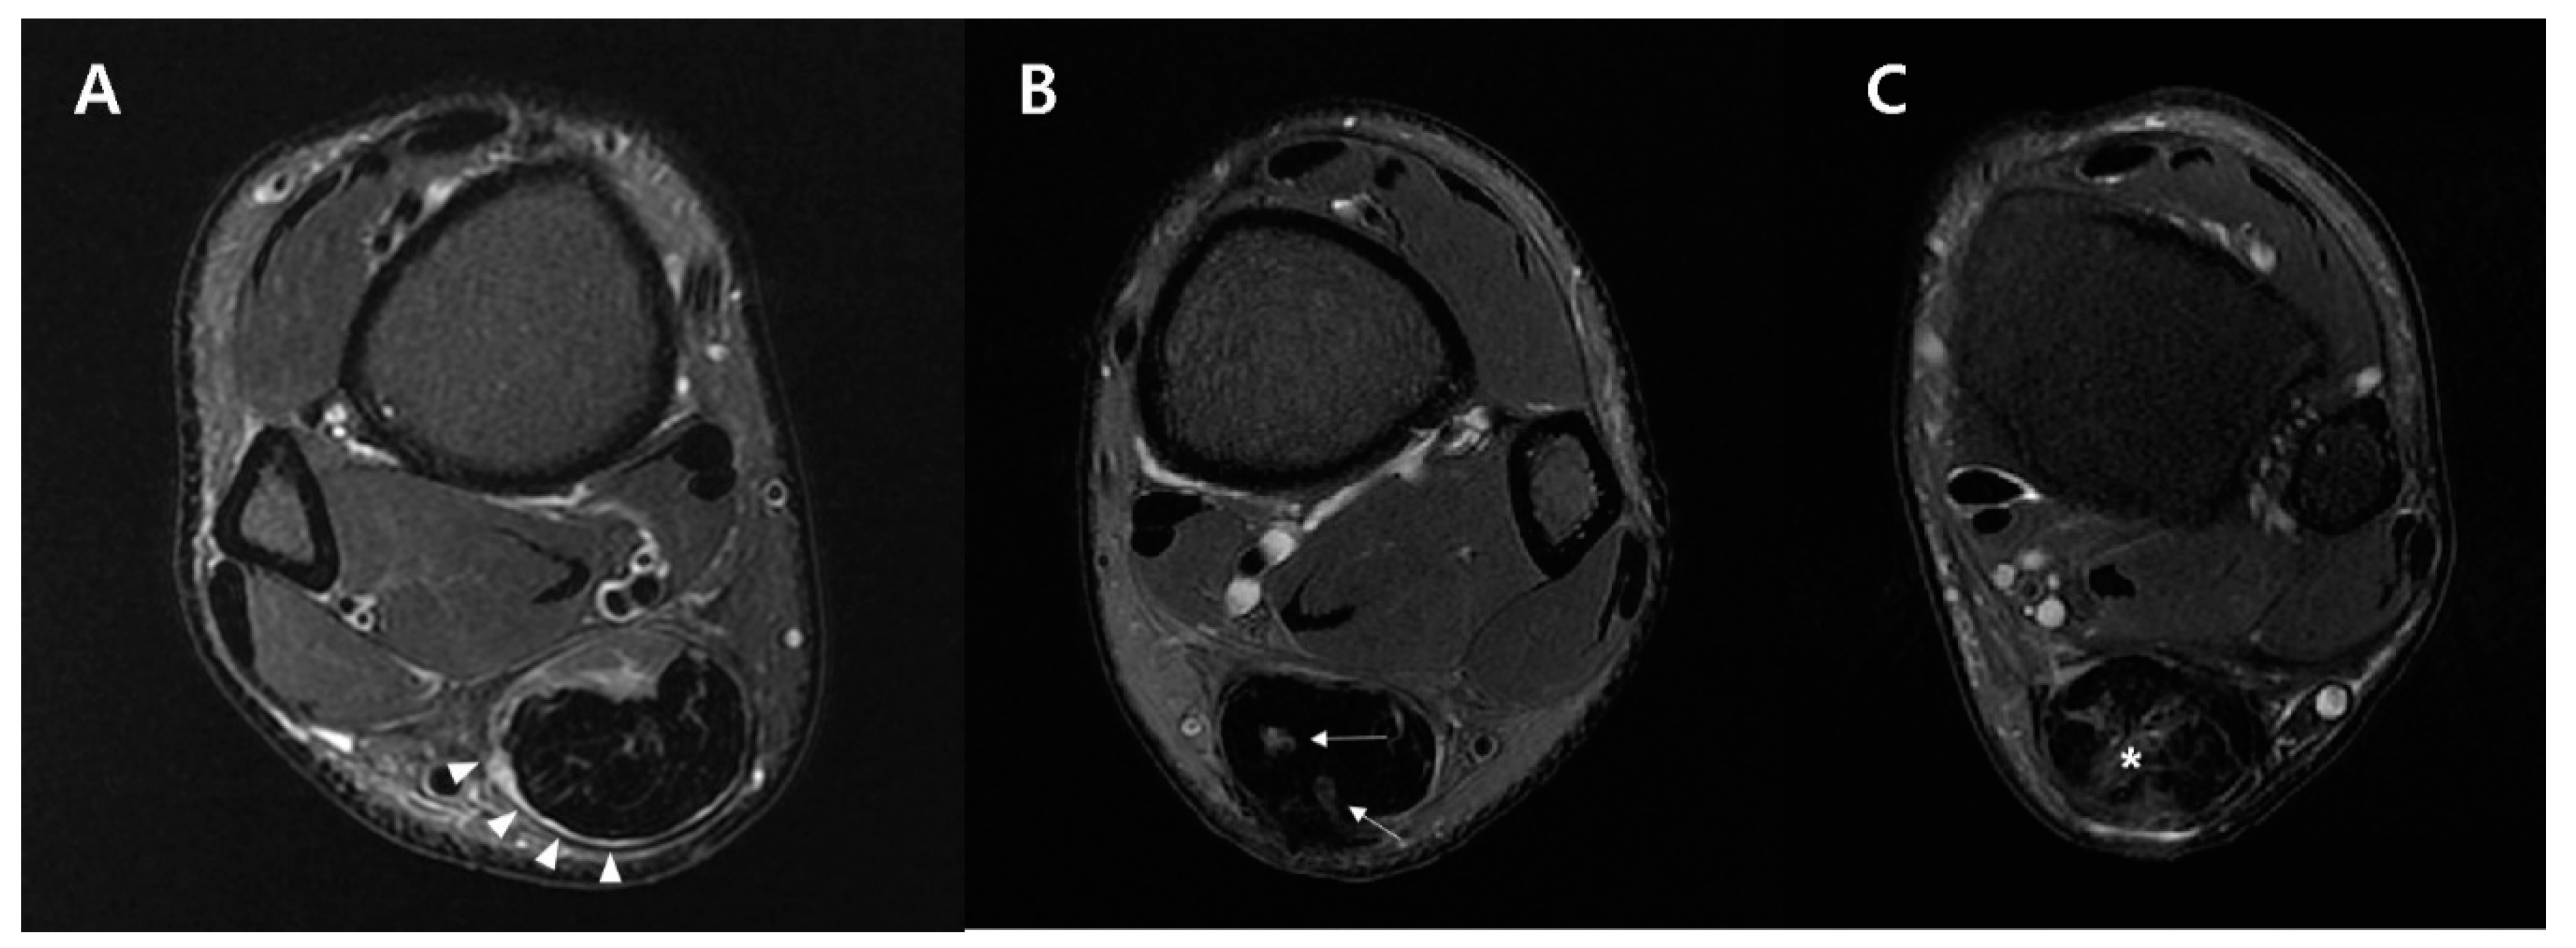

2.5.2. Fat-Saturated T2-Weighted Axial Image

| MTJ shape | 0.8204 | ||

| Convex | 4 (36.36%) | 6 (54.5%) | |

| Flat | 6 (54.55%) | 4 (36.4%) | |

| Concave | 1 (9.09%) | 1 (9.1%) | |

| Tendon signal changes | 0.7249 | ||

| Circumferential | 6 (54.55%) | 5 (45.4%) | |

| Focal | 3 (27.27%) | 3 (27.3%) | |

| Diffuse | 2 (18.18%) | 3 (27.3%) | |

| Postop circumferential area changes (times) | 2.43 ± 0.41 | 3.19 ± 0.51 | 0.0012 |